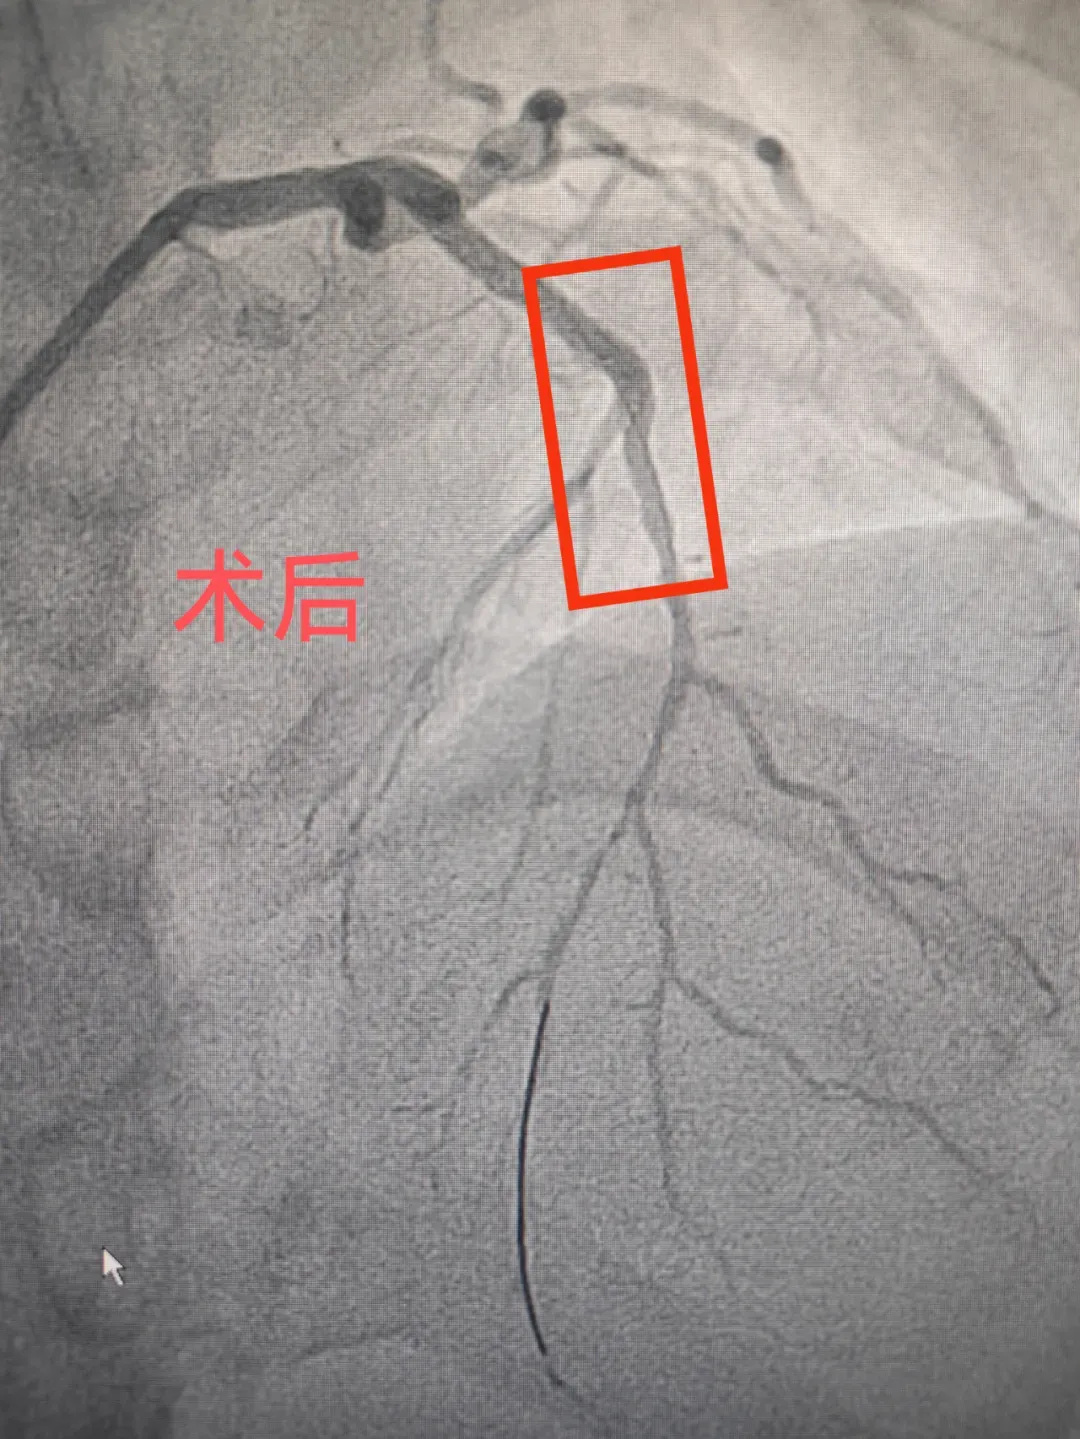

在心病科毛艳阳主任的带领下,医生们凭借着丰富的临床经验,迅速锁定了那条危及患者生命的关键“血管”,为患者小心翼翼地开通了冠脉。可挑战并未就此停止,患者出现了缺血再灌注心律失常,还伴有恶心、呕吐以及心源性休克等一系列症状。心内科团队沉着冷静地给予了积极处理,症状渐渐消失了,并为患者顺利植入了支架,让血流通畅起来,患者的心脏也得以重获生机。

延安市中医医院心病科毛艳阳介绍:“从患者踏入医院的大门,到冠脉成功开通,用时49分钟,也就是D-to-W时间,这一成绩完全达到了国家胸痛中心建设的严格标准。患者能够重获新生,得益于心病科、急诊科、介入导管室等多学科团队的默契配合,用心守护着每一位患者的心脏健康。”